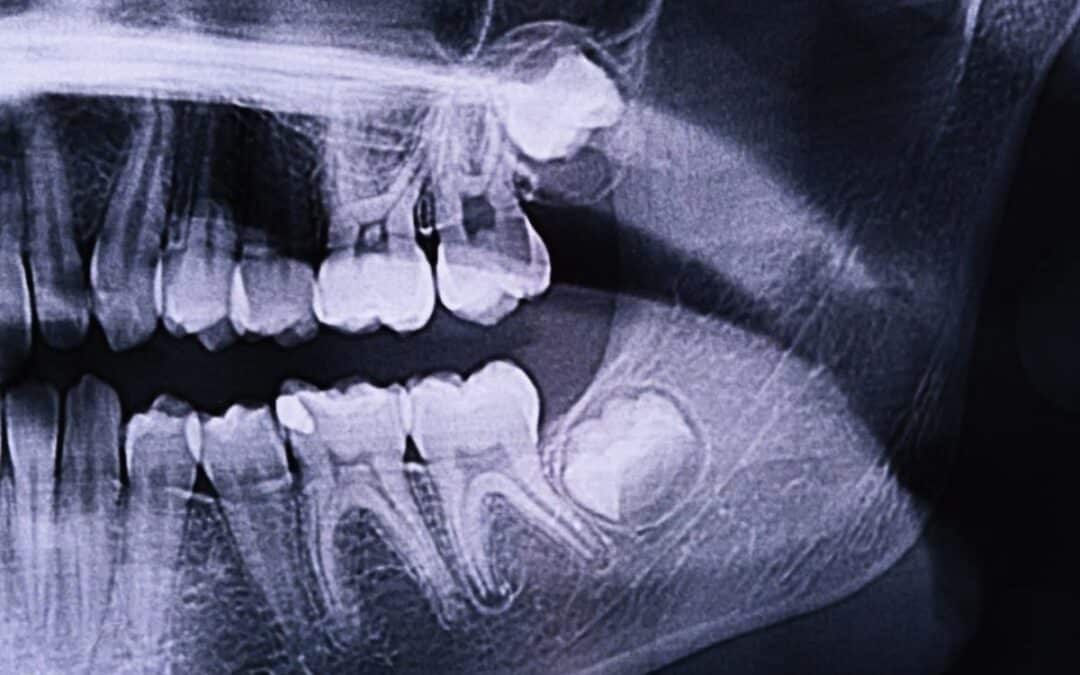

Guide To Early Signs of Wisdom Tooth Infection and What Treatment You Can Get

A person’s mouth is often too small to comfortably accommodate the extra four wisdom teeth that emerge in adulthood. This leads to constant pressure on the adjacent teeth, which ultimately results in pain. Molar teeth frequently come in at angles or slightly...